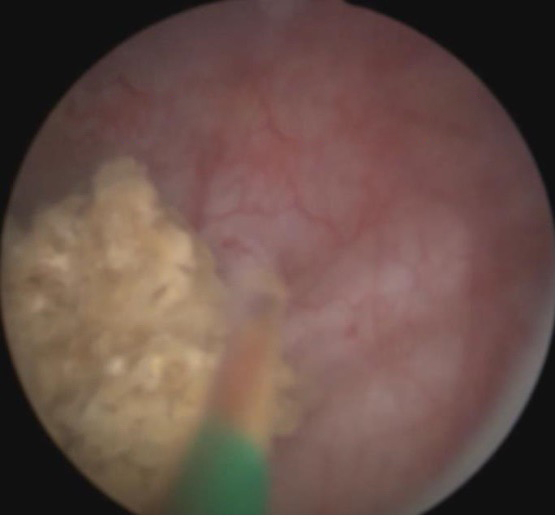

经尿道膀胱结石钬激光碎石术

该技术无需切口,通过尿道置入器械入膀胱,采用钬激光将结石粉碎后清除出体外。对肾输尿管结石排入膀胱而无法从尿道排出的情况,则需要行碎石术。对老年人膀胱结石,大多是继发于前列腺增生或者膀胱颈、尿道狭窄,则在术中清除结石后还需要同期处理这些原发致病因素,否则结石很容易再发。